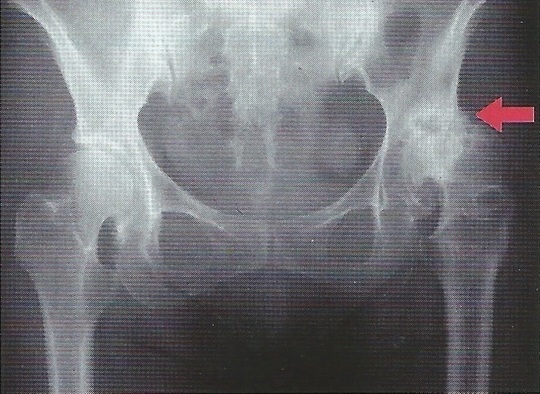

臼蓋形成不全

【診断】

問診、股関節の誘発痛可動域制限、X線像などで判断します。

臼蓋形成不全症